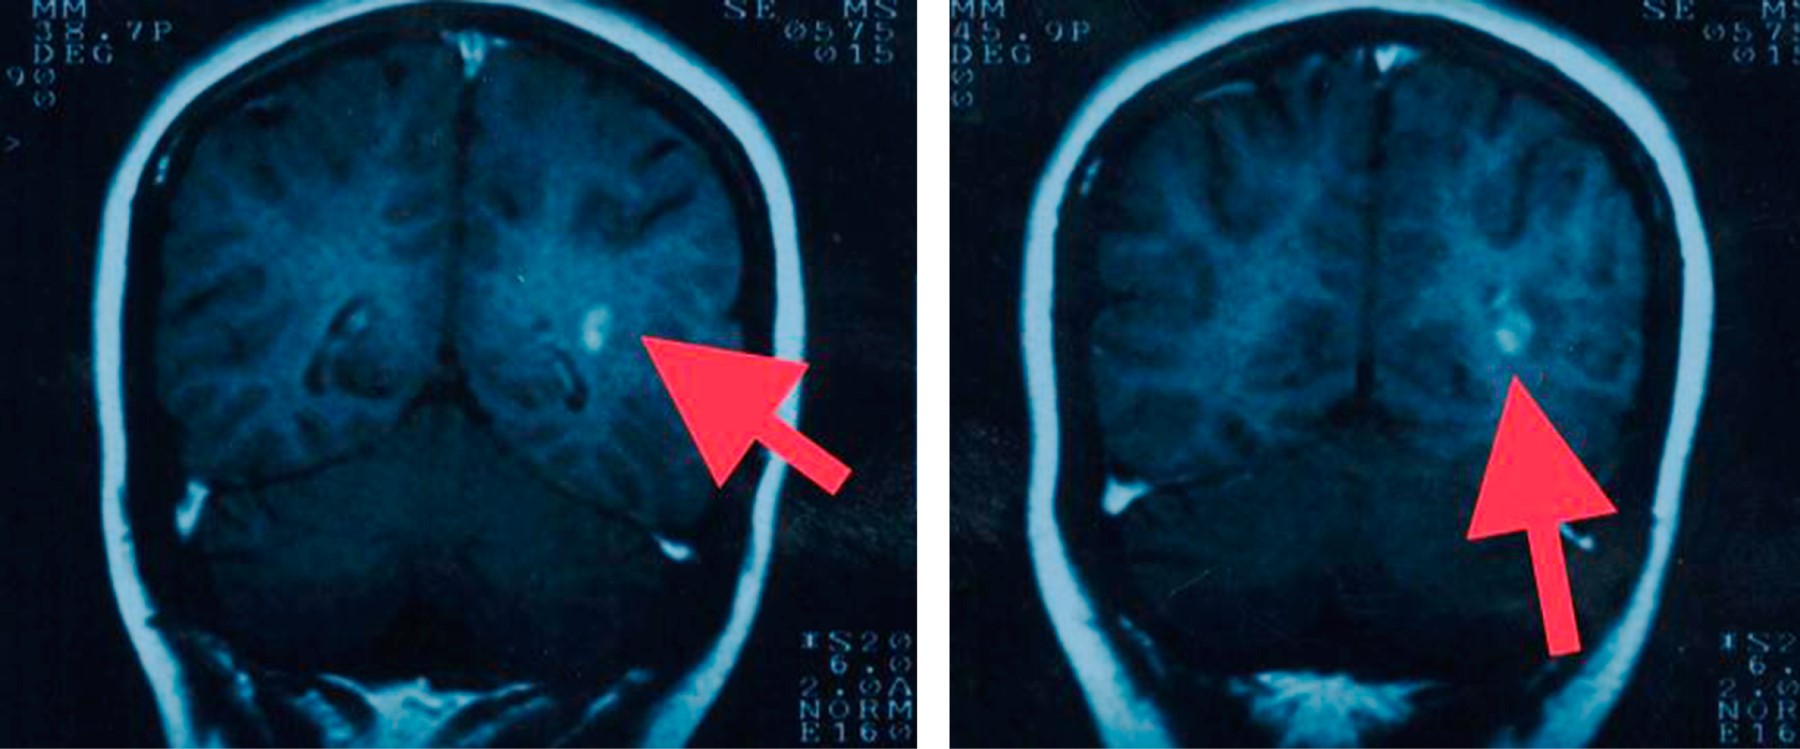

Objective: We describe two adolescent patients with multiple sclerosis, which is a demyelinating disease of the central nervous system. Presentation of the cases: The first case was a 14-year-old female patient with overweight; her condition was characterized by dizziness, headache, paresthesia in the lower limbs, diplopia and bradylalia. On physical examination, compatible data of cerebellar involvement were identified. A magnetic resonance imaging (MRI) of the skull showed areas of demyelination in the posterior fossa. Multiple sclerosis, the relapsing-remitting variety, is diagnosed. After the administration of steroids and beta interferon, there was improvement in symptoms. Second case: 13-year-old female, who presented fall from her own height, bladder incontinence, loss of strength in the left arm and leg. On physical examination, left hemiparesis was detected. MRI: demyelination data in lateral ventricle, cerebellum and spinal cord. The patient improved after starting steroids and interferon. Conclusions: The clinical presentation of multiple sclerosis in pediatric patients is a challenge, since it is a condition with unspecific manifestations. Establishing the diagnosis requires multiple studies. The earlier treatment is started, the more favorable the prognosis.

Figure 4

Figure 5